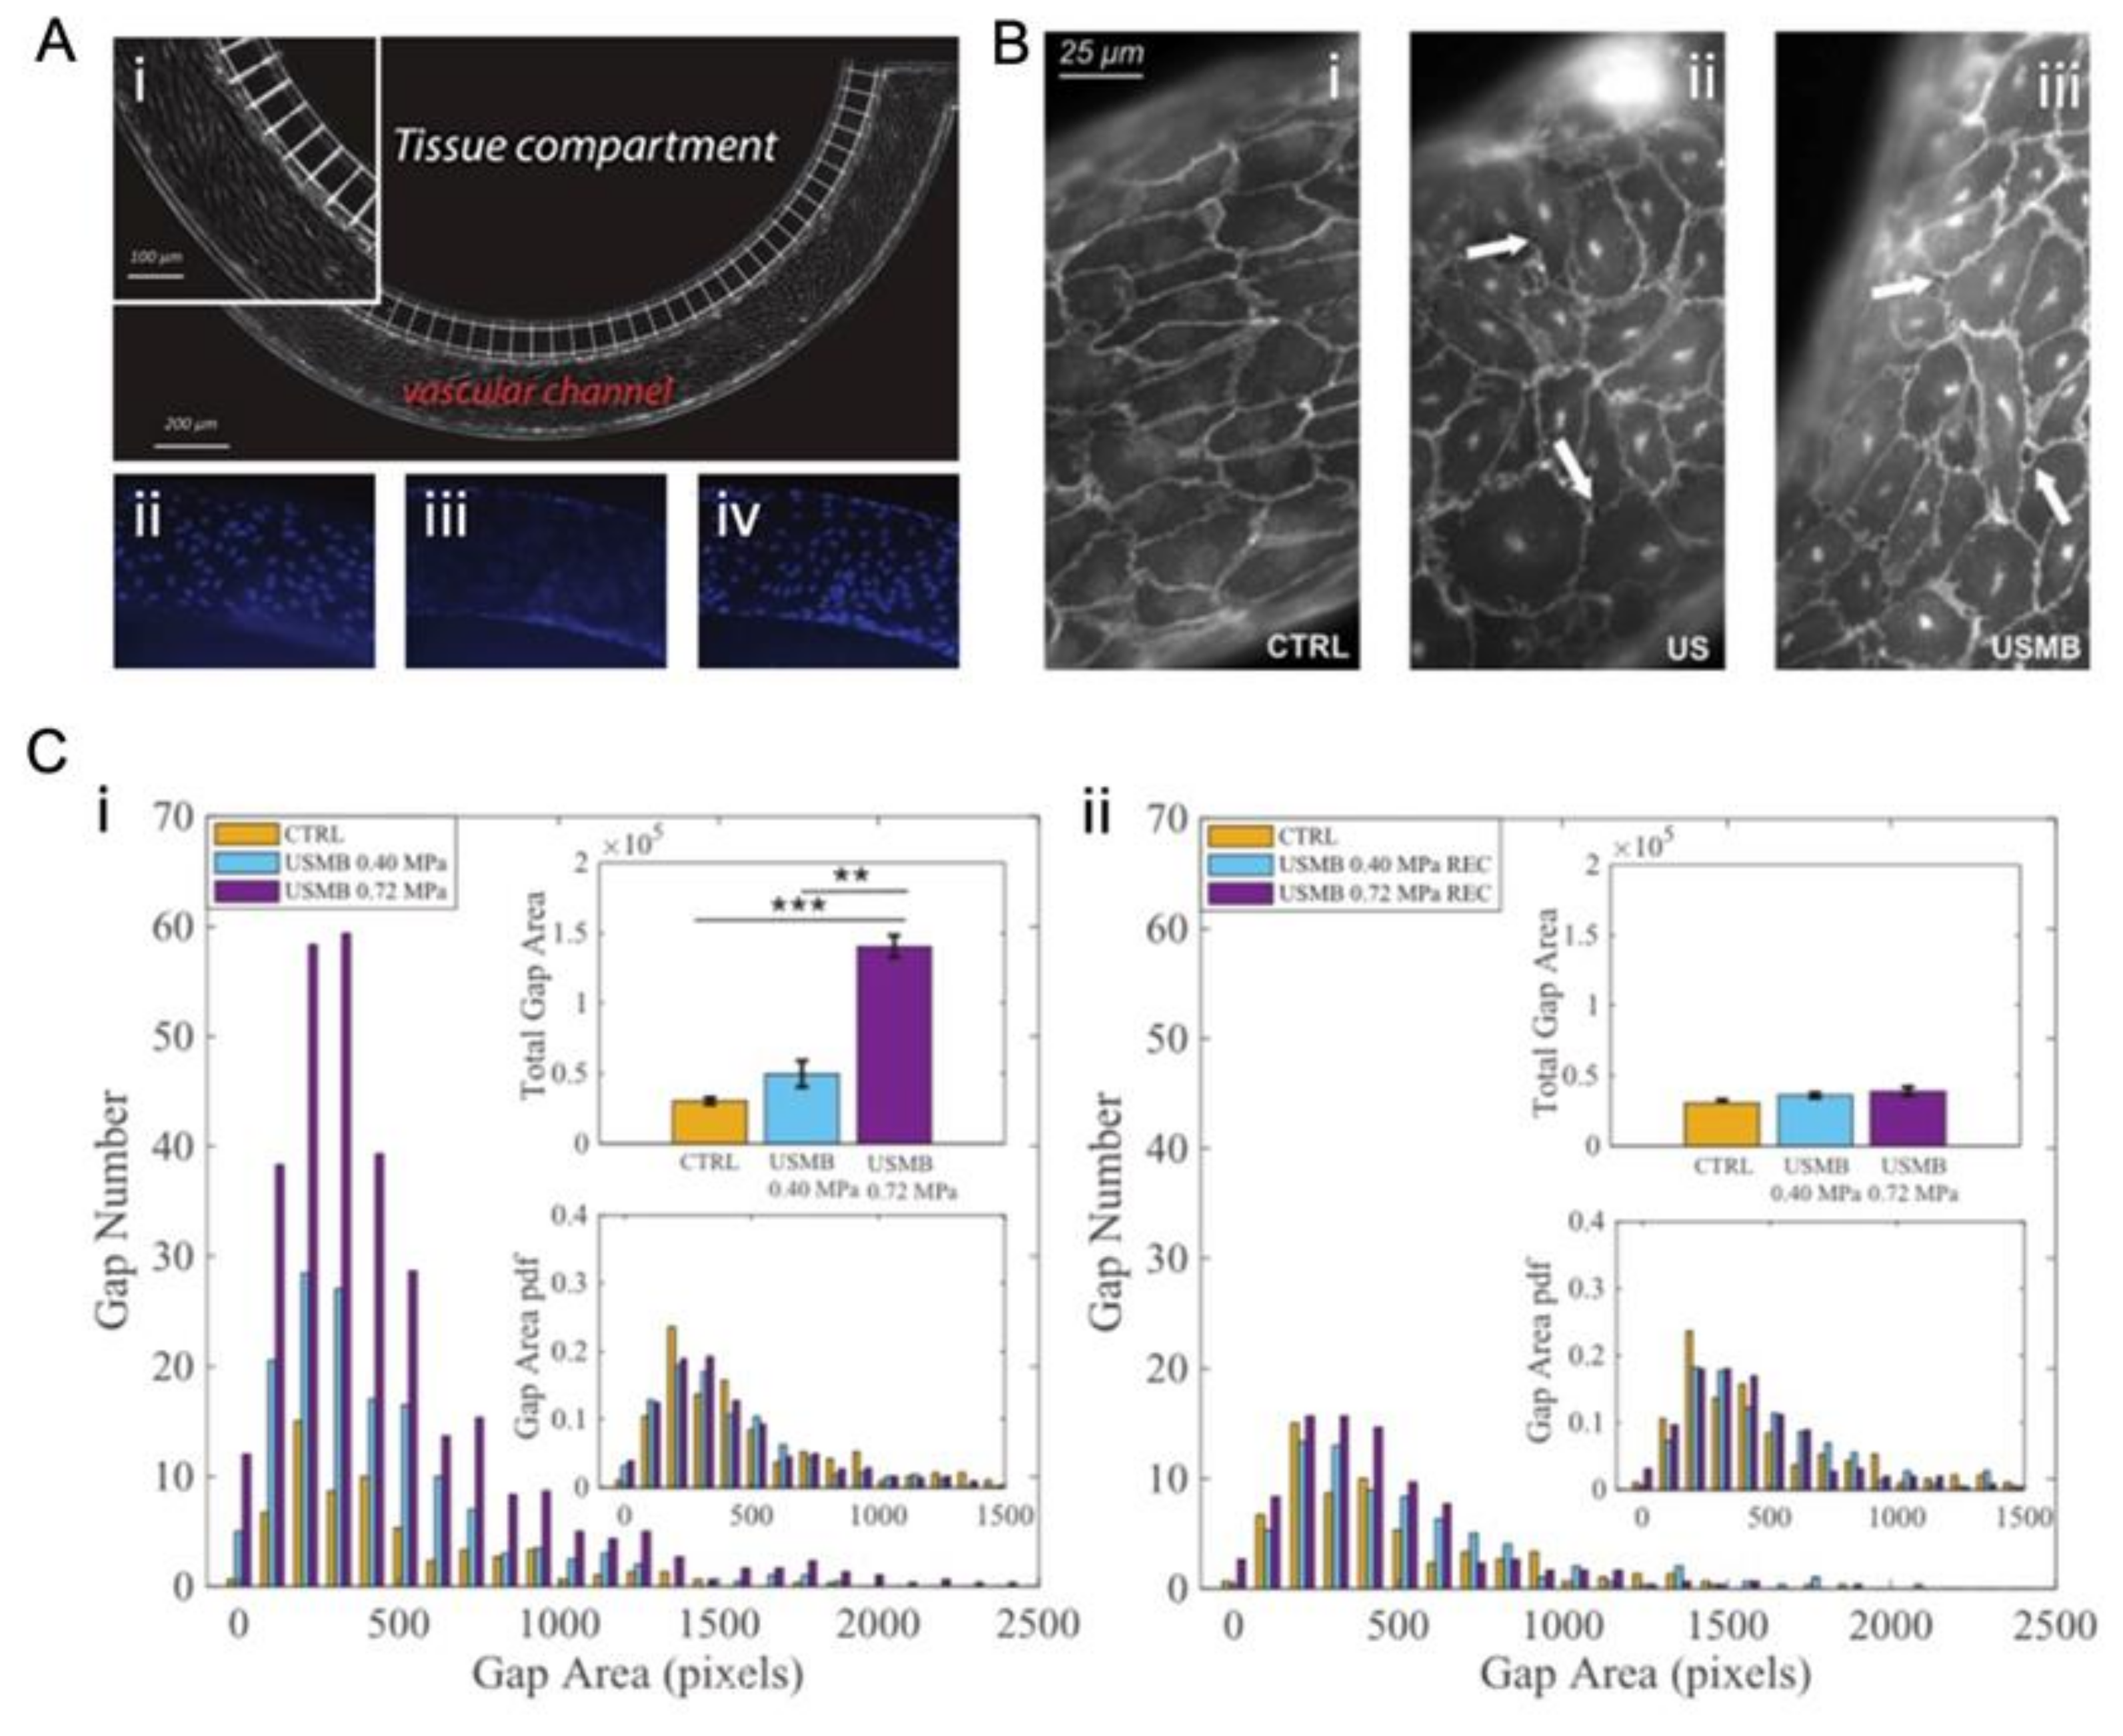

4.2.2. In Vitro Static System

- Silvani, G.; Scognamiglio, C.; Caprini, D.; Marino, L.; Chinappi, M.; Sinibaldi, G.; Peruzzi, G.; Kiani, M.F.; Casciola, C.M. Reversible Cavitation-Induced Junctional Opening in an Artificial Endothelial Layer. Small 2019, 15, e1905375. [Google Scholar] [CrossRef]